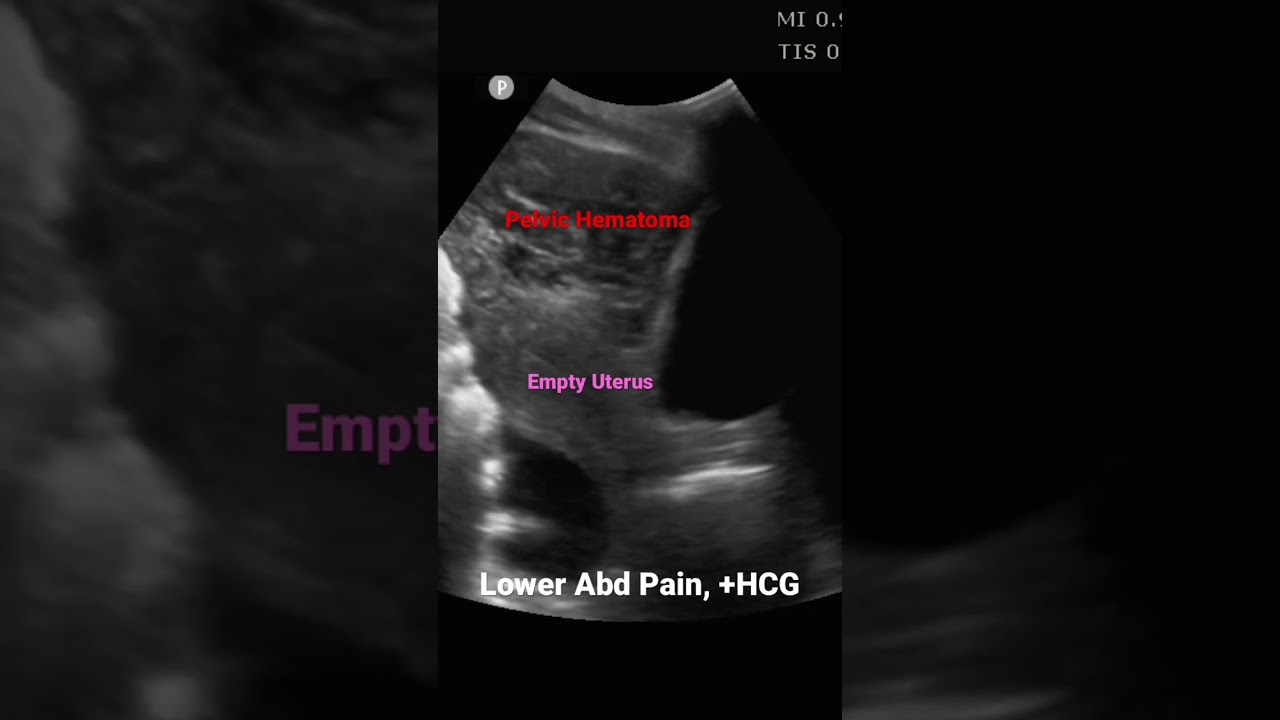

Ectopic Pregnancy Ultrasound 4 Weeks J Med Cases Ultrasound diagnosis of an ovarian ectopic pregnancy may be difficult to distinguish from ovarian germ cell tumours or other ovarian pathology. a high index of suspicion is based upon a combination of ultrasound findings (both grey scale and with colour doppler), as well as high levels of serum hcg and sonographic experience. Although vaginal spotting and lower abdominal pain are common in pregnancy, these are also typical presenting symptoms of tubal ectopic pregnancy and are indications for ultrasonography in.

Ectopic Pregnancy Ultrasound 4 Weeks J Med Cases Should a clinical presentation or abnormal pelvic ultrasound appearance suggest an ectopic pregnancy, despite visualization of an intrauterine gestation, the diagnosis of heterotopic pregnancy should be considered, with the probable need for diagnostic laparoscopy confirmation and treatment. This case highlights the importance of considering atypical presentations of ectopic pregnancy and the necessity of timely diagnosis and intervention to prevent adverse outcomes. The necessity to avoid overtreatment and the potential for iatrogenic harm in such cases has facilitated the introduction of expectant management into mainstream clinical practice. this represents one of the key developments in the care for women with ectopic pregnancies. Ectopic pregnancies primarily occur in the fallopian tubes, but can also be found in rare locations such as the broad ligament. this case report details a 27 year old patient with a 14 week ectopic pregnancy diagnosed in the broad ligament, illustrating the challenges in prenatal diagnosis.